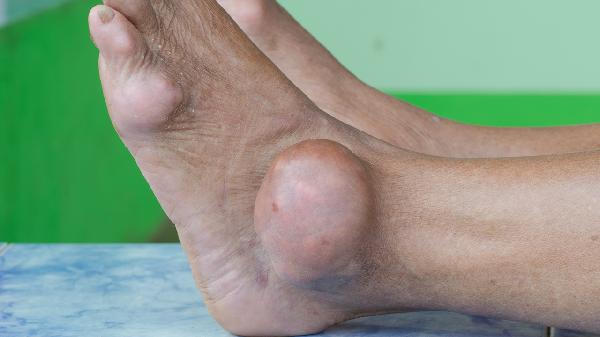

开放性骨折或术后伤口护理不当可能继发细菌感染,金黄色葡萄球菌等病原体繁殖会释放致热原。糖尿病患者或免疫力低下人群更易出现这种情况。骨髓炎早期可能仅表现为夜间低热,伴随患肢钝痛和皮肤发烫。长期使用抗生素者还需考虑真菌感染可能。